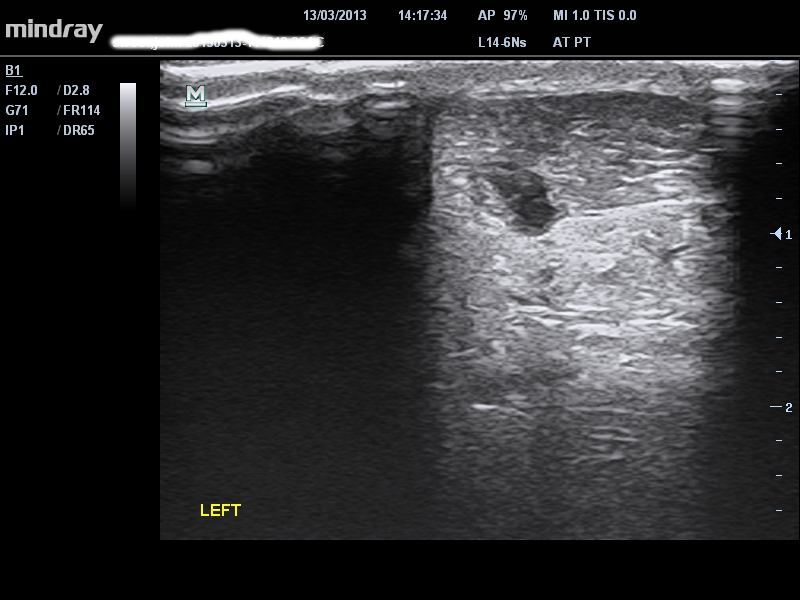

DESGARRO PARCIAL

Es necesario que presente los signos de diagnóstico claves para una rotura parcial– 1) un incidente definido que puedan recordar (¡y describir con precisión hasta el último detalle!); 2) dolor agudo/cambio definido en el dolor después del incidente; 3) pérdida aguda y mayor de fuerza, relacionada con la inhibición del dolor, este es un cambio importante en el dolor y la función que PODRÁ identificar a un kilómetro de distancia de una tendinopatía. La ecografía a menudo muestra lo que a veces se conoce como delaminación de la bolsa de grasa y el tendón, con una región hipo- o anecoica definida– es decir, un agujero negro, que es continuo en la periferia del tendón.

single-image

7 – región hipo/anecoica muy localizada en un paciente que presenta signos/síntomas de un desgarro